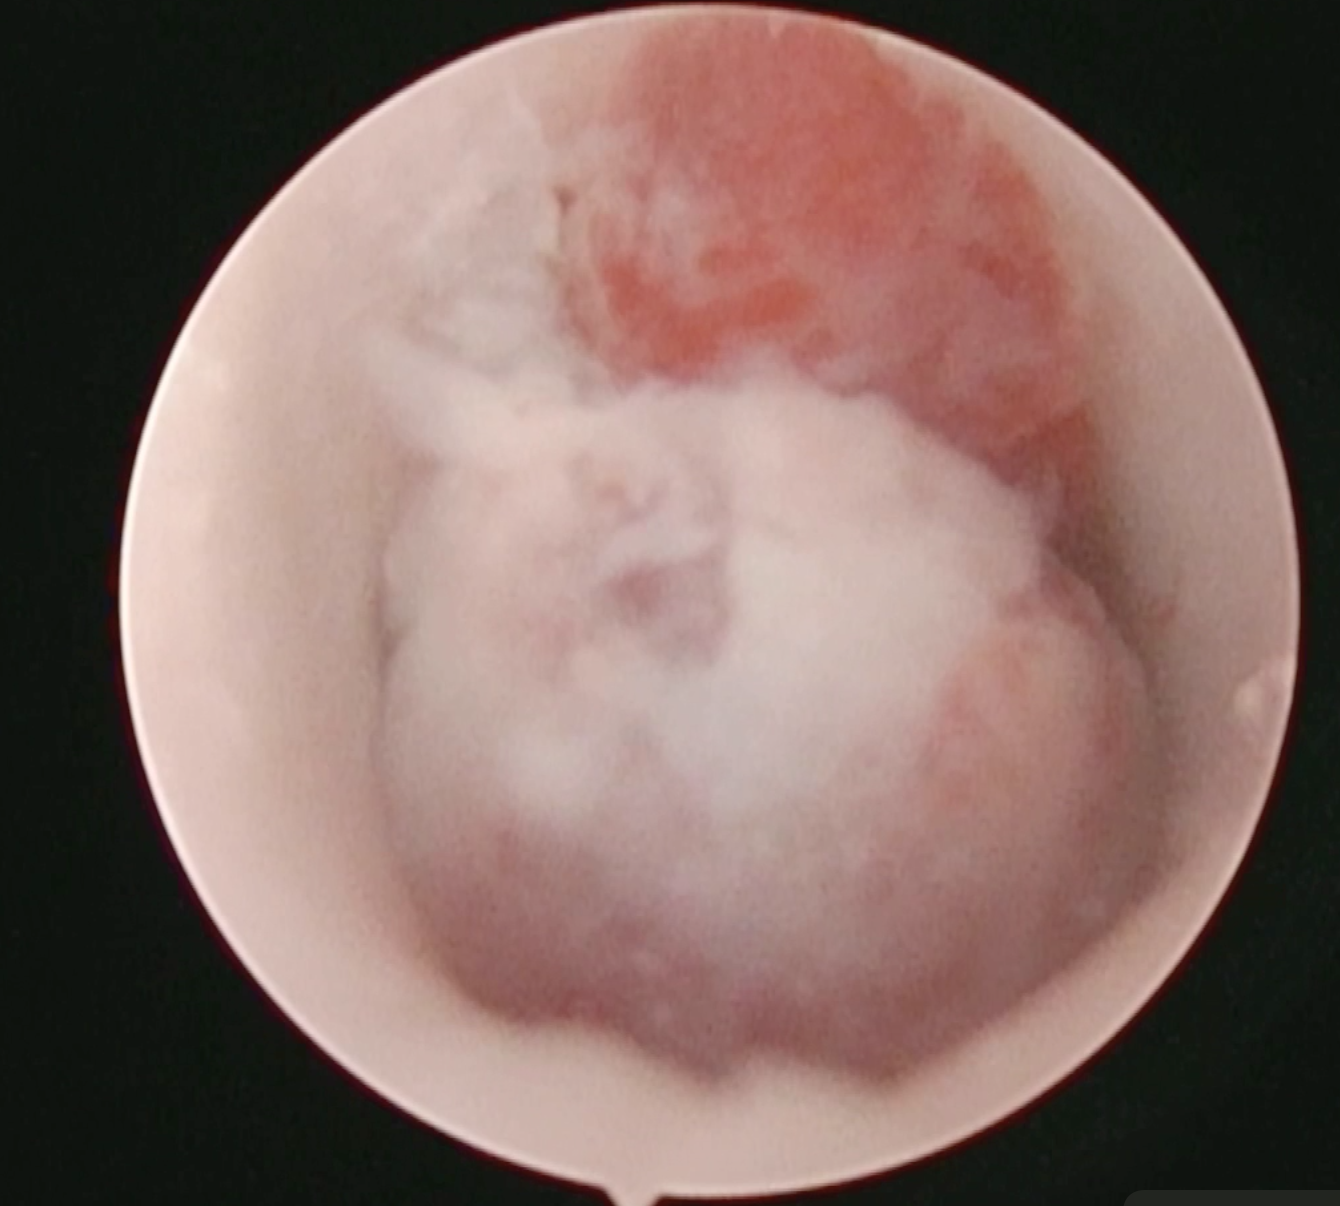

そして、耳の内視鏡であるオトスコープで腫瘤を直接確認しすることができます。

切除できそうなものなのかオトスコープで判断することができます。

耳の中の腫瘤